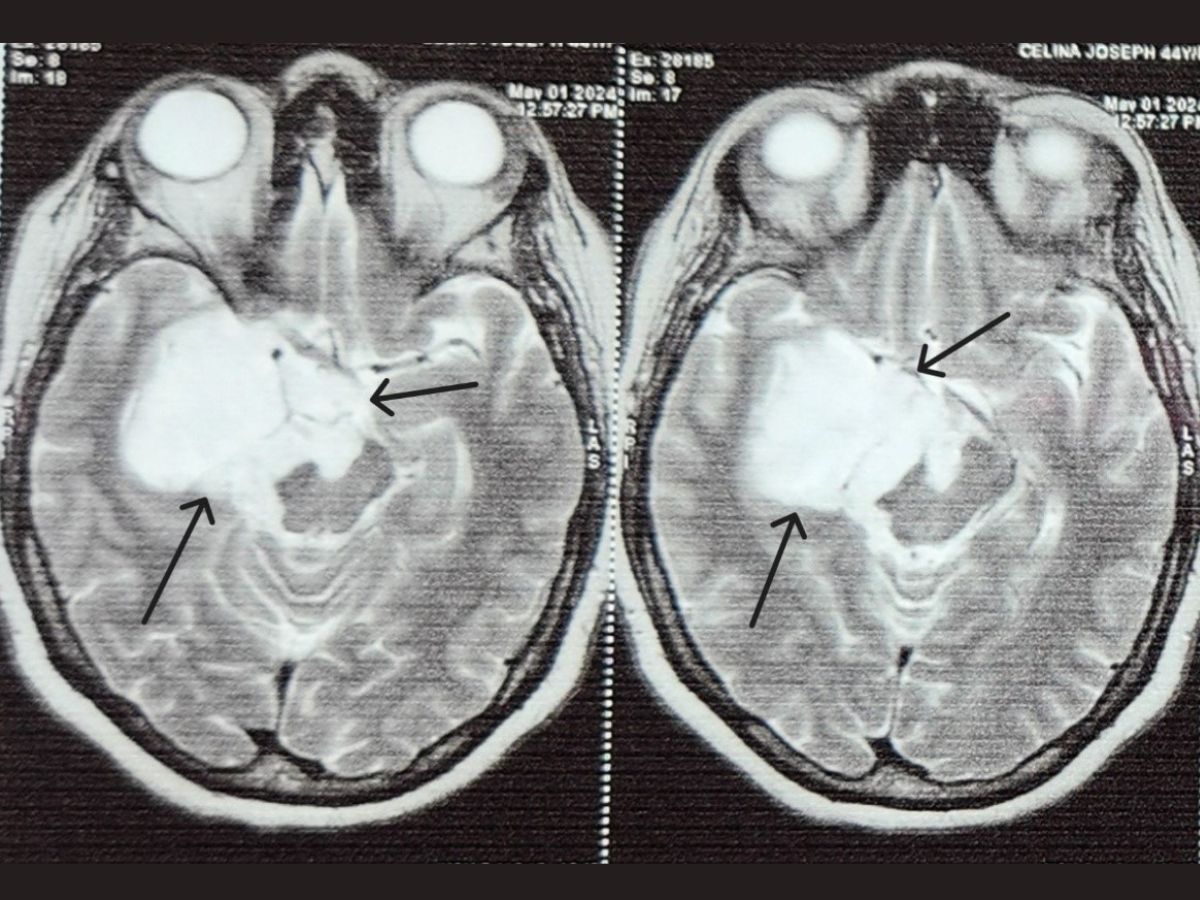

After an epidermoid tumor was found underneath a 45-year-old dessert chef’s brain through Magnetic resonance imaging who had recurrent seizures sought assistance from Dr. L H Hiranandani Hospital. The tumor had enveloped important nerves that help in vision and eye movement causing serious impairment of her sight and increasing the number of seizures.

Epidermoid tumors are non- cancerous, usually slow-growing masses occurring as a result of errors in cell migration during embryonic stage of development. These tumours contain a thick yellow substance called keratin and may compress neighboring areas of the brain leading to severe neurological symptoms.